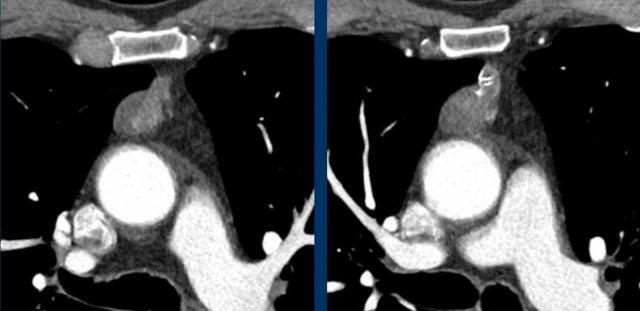

Các hình ảnh này của một nam giới 71 tuổi.

Trên CT ngực, tình cờ phát hiện một khối ở tuyến ức.

Hãy phân tích các hình ảnh. Nhận định của bạn là gì?

Hình ảnh

Một phần tổn thương có ngấm thuốc cản quang và có một số vôi hóa, có thể nằm ở thành nang.

Khi một tổn thương tuyến ức có thành phần đặc, nguyên tắc là… “khi còn nghi ngờ, hãy phẫu thuật cắt bỏ”.

Tổn thương đã được phẫu thuật cắt bỏ dựa trên kết quả CT và kết quả giải phẫu bệnh cho thấy đây là u tuyến ức dạng nang.